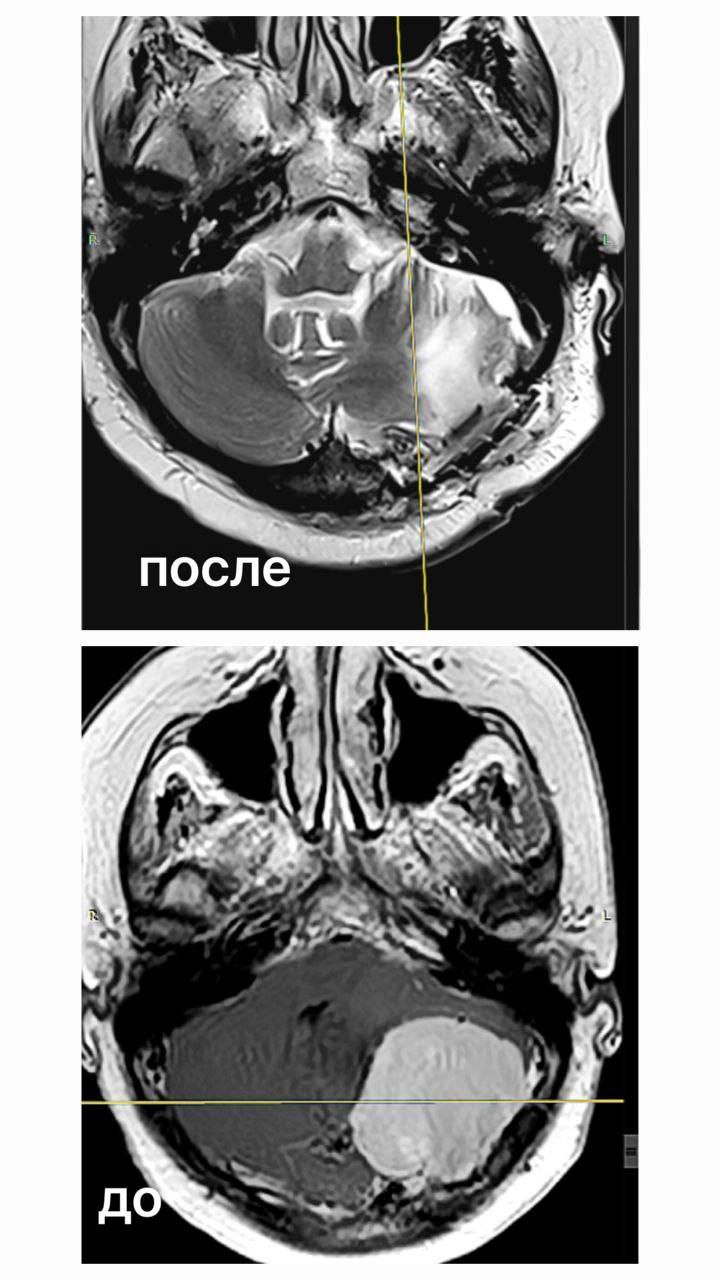

Была проведена магнитно-резонансная томография, которая выявила менингиому. Доброкачественное образование размером пять сантиметров занимало половину задней черепной ямки и сдавливало мозжечок.

«Нейрохирурги НГКБ №1 в течение 4,5 часов полностью удалили опухоль, сохранив целостность важных нервов. После восстановления женщина сможет самостоятельно передвигаться», — написал в своем телеграм-канале министр здравоохранения Кузбасса Андрей Тарасов.